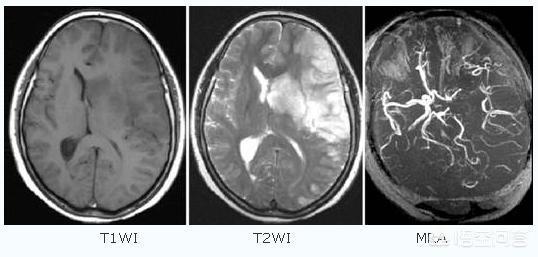

Son mari l'a emmené à l'hôpital, où une série d'examens d'imagerie ont été effectués et le diagnostic a été celui d'un infarctus cérébral. Le médecin a recommandé de procéder à un examen d'imagerie et d'enlever le caillot si nécessaire, ainsi que d'utiliser des médicaments pour contrôler les symptômes.

- Infarctus cérébralÉgalement appelée "infarctus cérébral", "thrombose cérébrale" ou "embolie cérébrale", elle se manifeste généralement par l'apparition soudaine d'une faiblesse ou d'un engourdissement d'un côté des membres, d'un engourdissement d'un côté du visage ou d'une déformation des coins de la bouche, et d'un manque de réactivité, une perte d'équilibre, des difficultés à avaler, des difficultés à parler, des troubles de la conscience ou des convulsions.

L'infarctus cérébral, également connu sous le nom clinique d'accident vasculaire cérébral ischémique, est un problème d'approvisionnement en sang des vaisseaux sanguins du cerveau causé par un certain nombre de raisons telles que l'athérosclérose, l'hypertension, le diabète sucré et les maladies coronariennes, entraînant une ischémie, une hypoxie et une nécrose des tissus cérébraux locaux.

Les accidents vasculaires cérébraux peuvent être divisés en deux catégories : les accidents hémorragiques cérébraux et les accidents ischémiques cérébraux. L'accident vasculaire cérébral ischémique (infarctus cérébral) est le type d'accident vasculaire cérébral le plus courant en Chine.L'accident vasculaire cérébral ischémique est un état dans lequel le flux sanguin vers le cerveau est insuffisant en raison de l'obstruction des vaisseaux sanguins, ce qui entraîne une nécrose ischémique et une perte de fonction des tissus cérébraux, l'embolie cérébrale et la thrombose cérébrale étant les causes les plus courantes. Avant l'apparition de l'AVC ischémique, les patients peuvent présenter des symptômes temporaires d'ischémie cérébrale (communément appelés mini-AVC), notamment l'apparition soudaine d'un engourdissement et d'une faiblesse unilatérale des bras et des jambes, des troubles de l'élocution, une vision floue, une perte d'équilibre, etc.Il s'agit d'un précurseur important de l'accident vasculaire cérébral... Les plaques d'athérome et la sténose des artères carotides cérébrales sont des facteurs importants de l'accident vasculaire cérébral ischémique.Outre les personnes d'âge moyen et les personnes âgées, les patients souffrant d'hypertension artérielle, d'hypercholestérolémie, de diabète sucré et les fumeurs de longue date constituent également les groupes les plus fréquents.